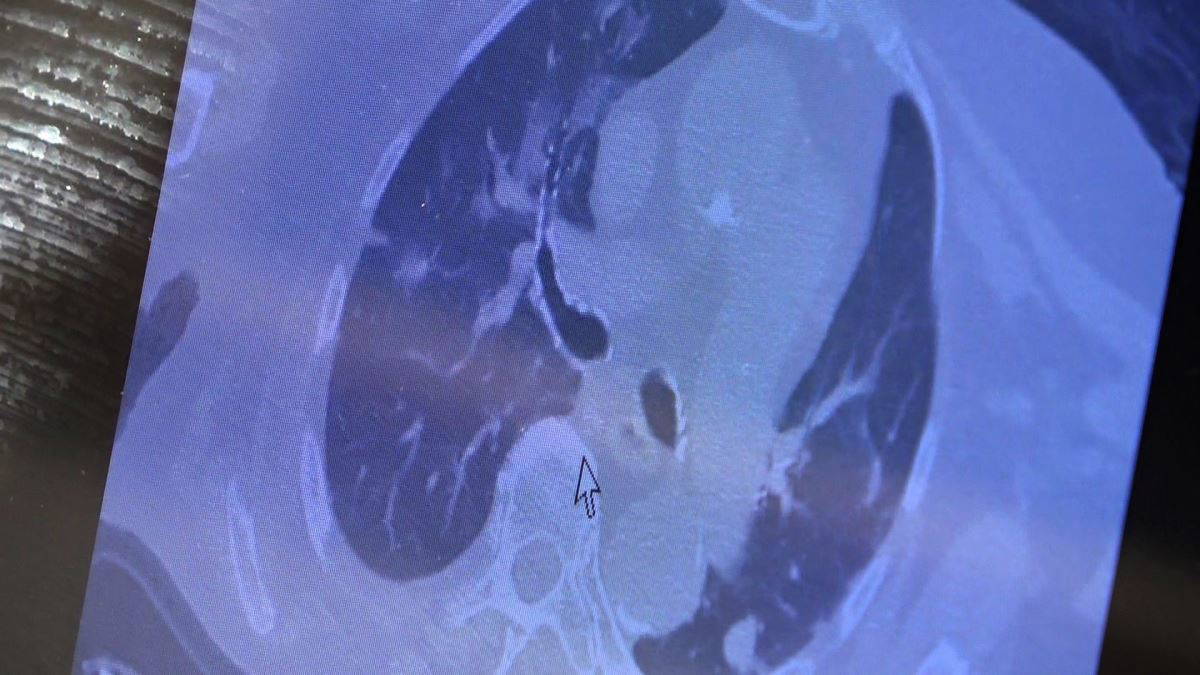

"Özellikle vatandaşlarımızdan aşı olurken kendilerini iyi değerlendirmelerini istiyoruz. Öyle vakalar geliyor ki ‘hocam biz 2 hafta önce aşı olduk, aşı olmamıza rağmen koronavirüs olduk’ diyen hastalar var. Ülkede hemen hemen herkeste subklinik yani şikayet yapmayan semptom vermeyen düzeyde de olsa virüs yükümüz var. Üzerine aşı olduğumuz zaman bu klinik aşikar hale geliyor ve doktora, hastaneye gelmekle sonuçlanıyor. Bunların bir kısmında gerçekten akciğer tutulumu da görüyoruz. Eğer kendiniz halsiz, yorgun, kırgın hissediyorsanız ve yakın çevrenizde pozitif vakalarla temasınız varsa lütfen aşı olmadan önce kendinizi değerlendirin. Birkaç gün gözlemledikten sonra aşınızı olmanızı istiyoruz. Yoksa kovid virüsü ile enfekte iken üzerine aşı olduğunuzda semptomatik hale geliyor ve özellikle iş gücü kaybı, panik hali oluyor. Hastalar ‘aşı oldum, hasta oldum’ kaygısı yaşıyorlar. Aslında öyle değil. Ülkemizde hemen hemen herkeste subklinik semptom vermeyen düzeyde de olsa hepimiz bu virüsle karşılaşıyoruz. Üzerine aşı olduğumuzda aşının oluşturduğu hafif kırgınlık ve ateşle beraber hastalık ortaya çıkmaya başlıyor. Şu ana kadar bu kadar vakalar artmasına rağmen ölüm sayılarının az olmasını ve hastaneye yatışların azalmasını aşıya bağlıyoruz. Her seferinde şunu tekrarlıyoruz: Aşı emniyet kemeri gibidir. Sizi kaza yapmaktan ya da hastalıktan korumaz ama kaza yaptığınızda veya hastalığa yakalandığınızda hayatta kalmanızı sağlayacak."

Karşılaştıkları bu yeni hasta profilini örnek vererek açıklayan Özkaya, "81 yaşındaki bir hasta. Ailesinde kovid pozitif biri varken panik yaparak aşıya gidiyor. Sonrasında hızla akciğer tutulumu olan bir hasta ile karşılaşıyorsunuz. Bu şekilde ailenizde pozitif biri varsa ve kendinizde halsizlik kırgınlık hissediyorsanız panik yapmadan önce doktora gitmenizi sonra aşı olmanızı istiyoruz. Şu an ‘aşı oldum hastalandım’ diyenlerin büyük bir kısmı subklinik olarak virüsle enfekte iken aşı olan grubu oluşturuyor" şeklinde konuştu.